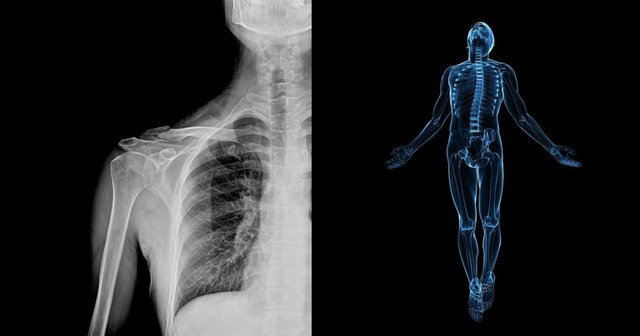

توریست مالزی- فناوری شرکت مهندسی پزشکی “Zebra-Med” در ازای تنها یک دلار برای هر اسکن کامل بدنی، به رادیولوژیستها کمک میکند تا بیماریهای قلبی، کبدی، ریوی، استخوانی و غیره را تشخیص دهند.

یک شرکت به نام “Zebra Medical Vision” یک سرویس جدید را به نام “Zebra AI1” معرفی کرده است که از الگوریتمهایی برای بررسی اسکن پزشکی شما به ازای یک دلار استفاده میکند.

موتور یادگیری عمیق میتواند سی تی اسکن، ام.آر.آی (MRI) و دیگر اسکنها را بررسی کرده و به طور خودکار بیماریهای ریوی، کبد، قلب و استخوان را تشخیص دهد. مسؤولان این شرکت میگویند: تواناییهای جدید مانند تشخیص سرطان ریه و سرطان سینه، ترومای مغزی، فشار خون بالا و دیگر موارد به زودی ممکن میشود.